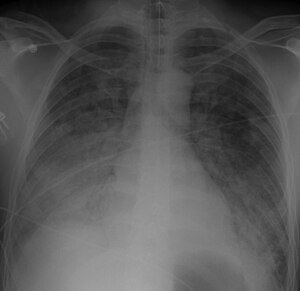

Chest Xray 40 yr old male acute respiratory distress syndrome as a complication of murine typhus. 13-1421-F1.jpg

Chest X-ray of a 40 yr old with acute respiratory distress syndrome as a complication of murine typhus